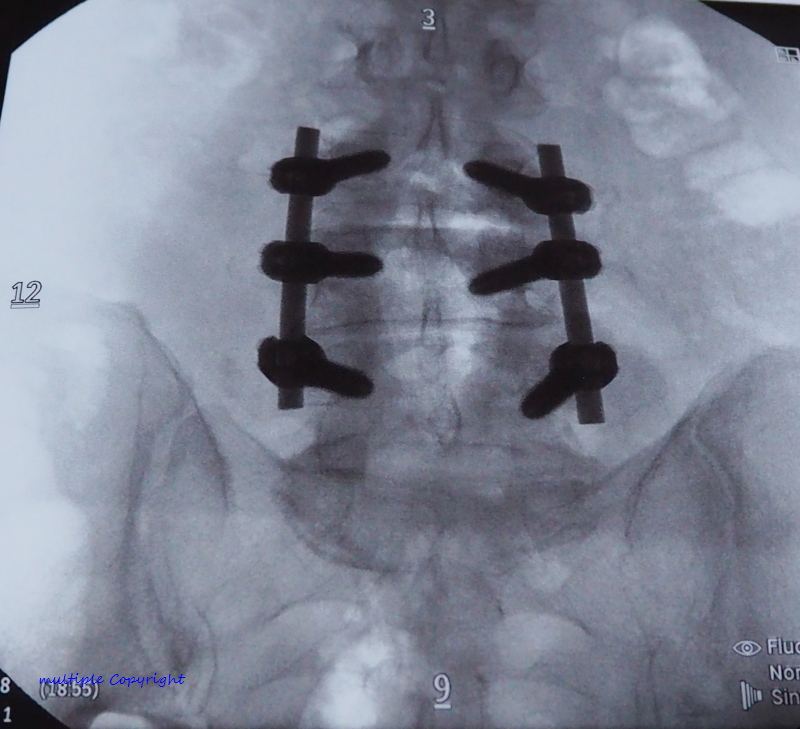

3. อวัยวะล่าสุด ที่ถูกเปลี่ยนก็คือ แกนกลาง ลำตัว Titanium ที่เป็นโลหะเบา แต่แข็งแกร่งพอๆกับเหล็กกล้า ทนทานต่อการกัดกร่อน ทนต่อความร้อนสูงและแรงเสียดสีเวลาใช้งานหนัก และยังไม่เป็น สื่อแม่เหล็ก สามารถผ่าน เครื่องสแกนทุกชนิดได้ ... เปิดตัว Project Titanium มานี่ ยังกับหนัง คนเหล็ก 3กำเนิดใหม่ เครื่องจักรสังหาร เลยนะครับ5555 เพื่อนๆแฟนคลับ คงทราบข่าว ว่า อาจารย์เต๊ะ ไป ผ่าตัด กระดูกสันหลัง มากันแล้วนะครับ มาครับมา เตรียมปูเสื่อ ข้าวโพดคั่ว ส้มตำปูปลาร้ามา กันเลย เดี๋ยว อาจารย์เต๊ะ จะเล่าให้ฟังนะครับ ....

.... พูดถึงการผ่าตัดครั้งนี้นี่ ฟังจากปากพี่สาวที่ คุณหมอ บอก มาเล่าให้ฟังว่า เคส อาจารย์เต๊ะ ค่อนข้างยากและซับซ้อน เพราะกระดูกทั้งเคลื่อน ทั้งกดทับเส้นประสาทด้วย ต้องใช้หมอ เฉพาะทาง ถึง 2 คน มาช่วยกันผ่า โชคดี คุณหมอมี พี่น้องฝาแฝด เป็นหมอกระดูกเหมือนกันด้วย เลยได้มาช่วยผ่าด้วยกัน แล้วก้จริงๆ คุณหมอนี่เชี่ยวชาญการผ่าโดยใช้ หุ่นยนต์มาก แต่ เคส อาจารย์เต๊ะ ยากเกิ้นนน ต้องผ่าแบบธรรมดาแผลใหญ่

แต่ถึงจะยากแค่ไหน ด้วยประสบการณ์คุณหมอ ก็สามารถผ่าได้สำเร็จ เรียบร้อยดี